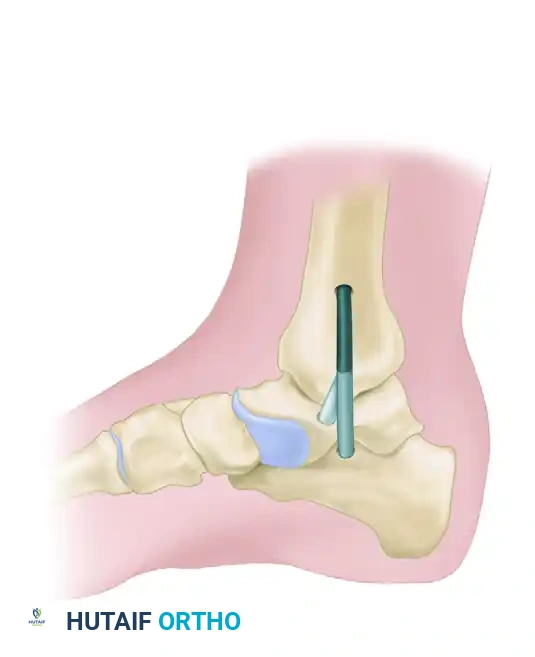

- Create a tibial tunnel by inserting a guidewire parallel to the joint surface at the level of the distal tibial physeal scar. The wire must be centered in the sagittal plane within the tibia.

- Confirm the guidewire position with multiplanar fluoroscopy.

- Drill a 6.5-mm tunnel to a depth of 25 mm over the wire.

- Insert the intact (nonsplit) end of the tendon graft into this blind tunnel. Fix it securely in place with a biotenodesis screw. Bioabsorbable polylactic acid interference screws of 6.25 to 8.0-mm diameter are recommended, selected based on the patient's local bone density.

- With digital palpation, locate the medial border of the sustentaculum tali. Advance a guidewire for a biotenodesis screw along an axis from the sustentaculum tali to a point approximately 1 cm superior to the peroneal tubercle on the lateral side of the calcaneus.

- Confirm the position of the guidewire with fluoroscopy, and create a 5-mm tunnel over the guidewire.

- Pass the free end of the remaining limb of the tendon graft through this calcaneal tunnel.

- Manually tension the graft to obtain a congruent tibiotalar joint position on fluoroscopy. Insert a 5.5-mm interference screw from medial to lateral into the calcaneal tunnel.